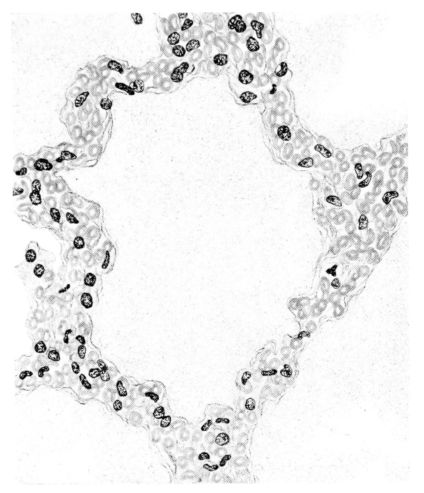

FIG. IV. AUTOPSY NO. 205. CONGESTION AND EDEMA OF THE SUBMUCOSA AND REGENERATION OF THE TRACHEAL EPITHELIUM.

The changes are less marked, perhaps, in the trachea than in its finer ramifications. The mucosa is constantly more or less destroyed and large areas, usually focal, are entirely devoid of their epithelial covering. This is replaced by a sparse exudate, composed largely of red blood cells, mucus, a small amount of fibrin, and nuclear fragments (Fig. II). It may dip into the submucosa for a short distance, but usually these indentures are associated with the ducts of the mucous glands into which the inflammatory reaction extends. A more striking feature than the exudate, however, is the edema and the congestion of the submucosa. The loose areolar tissue of the submucosa is spread widely apart, and throughout it distended blood vessels are very conspicuous. Occasionally such a vessel is broken and actual hemorrhage appears in the submucosa. Occasionally, too, the inflammation extends down the duct to the mucous gland itself, and here, also, aplastic inflammatory reaction is evident, inasmuch as the acini now stain intensely red with the cells undifferentiated from each other and specked here and there by broken remains of the dead nuclei (Fig. III). After the disease has continued for a short period, even at the end of five or six days, some regeneration of the epithelial lining may be seen (3) (Fig. IV). But despite this, the acute picture persists, and there goes on, side by side, an attempted repair characterized by epithelial regeneration and the same evidence of acute change. Since the lesion is essentially a superficial one, scars or contractures of any extent are not encountered in the trachea, even in examples of the disease that have ended fatally only after many weeks.[4]